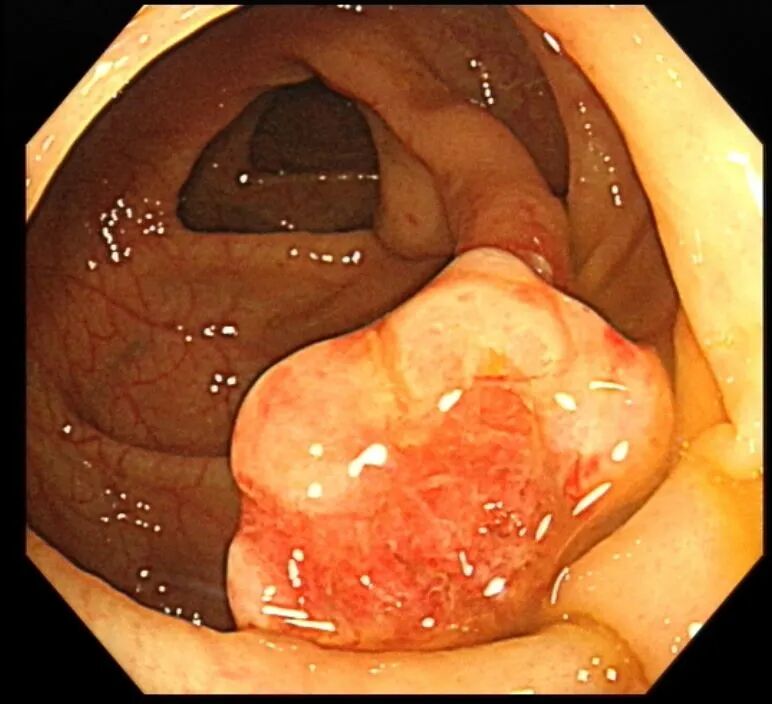

接诊的消化内科医生详细询问了小金的便血特点、发病时长和生活习惯,敏锐意识到这绝非普通痔疮那么简单,当即给他安排了无痛结肠镜检查。负责操作的徐思楠医生在肠镜进镜时,刚进入直肠就看到肠腔内残留的暗红色血迹,循着出血踪迹一路探查,最终在降结肠找到了出血的“元凶”——一枚长径接近3cm的粗长蒂息肉,它的外形就像一颗胖乎乎的蘑菇,蒂部粗壮坚韧,息肉头部表面已经出现了明显的糜烂和渗血,这正是小金反复便血的根源。

考虑到息肉体积大、蒂部粗壮,内部极可能存在粗大的滋养血管,直接切除极易引发术中、术后出血,徐思楠医生当机立断,在和小金妈妈充分沟通、取得书面知情同意后,当场为小金制定了缜密的手术方案,在手术过程中,徐医生先用数枚钛夹精准夹闭息肉的粗蒂根部,彻底阻断息肉的血液供应,再用圈套器完整套住息肉头部,通过规范的电凝电切操作将息肉完整切除,最后再用钛夹严密封闭手术创面,全程几乎无明显出血,操作顺利完成。术后,小金转入住院部,接受了规范的禁食、静脉补液、营养支持等治疗,未出现出血、穿孔等并发症,很快恢复了正常饮食,顺利康复出院。术后病理结果最终揭晓,这枚息肉为幼年性息肉,属于良性病变,后续只需定期复查肠镜即可。